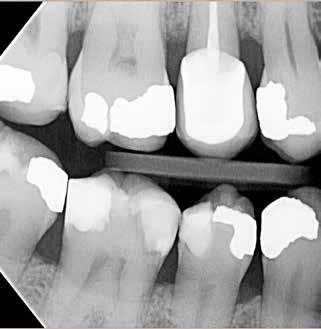

ÅR EN RODBEHANDLET TAND har nået et punkt, hvor tandsubstansen er stærkt reduceret pga. cuspisfraktur, caries, fyldninger eller som følge af endodontisk behandling (Fig. 1A og B), kan det være indiceret, at tanden genopbygges med stift, opbygning samt støbt restaurering (1-5). Førstnævnte for at opnå tilstrækkelig retention af opbygningen. Det er udbredt, at guttaperkafjernelse er mekanisk baseret med anvendelse af et roterende bor (Fig. 1C) (3,6). Boret placeres over rodfyldningen, hvorefter den koronale del samt noget af rodkanalvæggen fjernes mekanisk (4). Den mest apikale del af rodfyldningen bibeholdes, for at denne fortsat er tæt (2,3). En af udfordringerne ved en optimal guttaperkafjernelse samt stiftudboring er muligheden for at følge rodfyldningen uden at afvige fra rodkanalen (7,8). Perforation af tandroden kan ske ved ukorrekt vinkling (Fig. 1C og D), og risikoen forstærkes yderligere ved kraftigt reduceret tandsubstans i den cervikale del af kronen (9,10). Inspektion og belysning kan være besværliggjort, og endelig kan rodfyldningen være meget hård, hvilket komplicerer den taktile sansning under præparationen (9,11). Den utilsigtede vinkling af stiftudboringen, ultimativt rodperforationen,

Fig. 1. Radiologisk sekvens efter en rodperforation i forbindelse med en stiftpræparation i en underkæbemolar (-6). A. Røntgenbillede før rodbehandling. Rodkanalmorfologien viser, at den distale rod har to adskilte rodkanaler (pil). B. Rodbehandling afsluttet og kontrolleret. C. Initial mekanisk fjernelse af rodfyldning. D. Efter mekanisk fjernelse af rodfyldning ses en retningsafvigelse i forhold til den nederst beliggende rodfyldning. E. En midlertidig fyldning af rodkanalen viser rodperforationen (pil). Der er indhentet patientsamtykke til visning af røntgenbilleder.

Fig. 1. Radiologic sequence after root perforation in connection with mechanical preparation of a post in a mandibular molar (-6). A. Radiograph before the procedure. The morphology of the root canal shows that the distal root has two separate root canals (arrow). B. Procedure completed and controlled. C. Initial mechanical removal of root filling. D. After the mechanical removal of root filling the direction of the drill deviates from the lowest part of the root filling. E. A temporary filling of the root canal shows the root perforation (arrow). The pictures are used with the permission and consent of the patient.